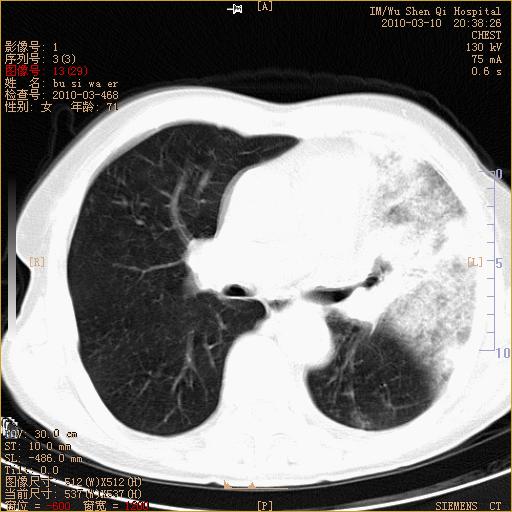

以下是引用随光逐影在2010-3-11 0:41:00的发言:[br]1)考虑左肺及右肺上叶继发性肺结核并左肺炎症感染。2)左侧支气管内膜结核可能;建议必要时行纤支镜检查。3)肺气肿。4)心包膜增厚(或少量心包积液)。5)左侧胸腔积液。